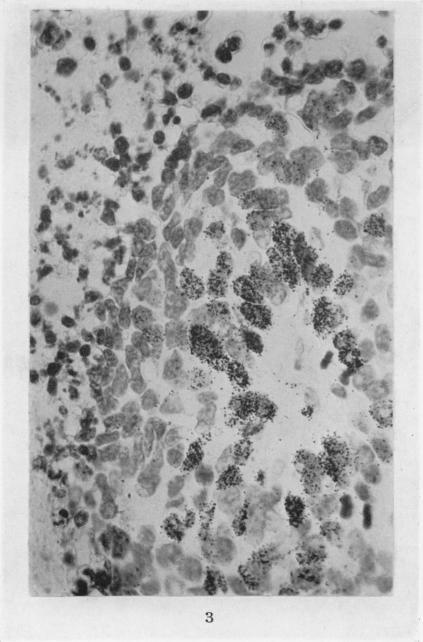

The relation between cell proliferation and the vascular system in a transplanted mouse mammary tumour.

Br J Cancer. 1968 Jun;22(2):258-73. doi: 10.1038/bjc.1968.34.

The relation between cell proliferation and the vascular system in a transplanted mouse mammary tumour.移植的小鼠乳腺肿瘤中细胞增殖与血管系统之间的关系。